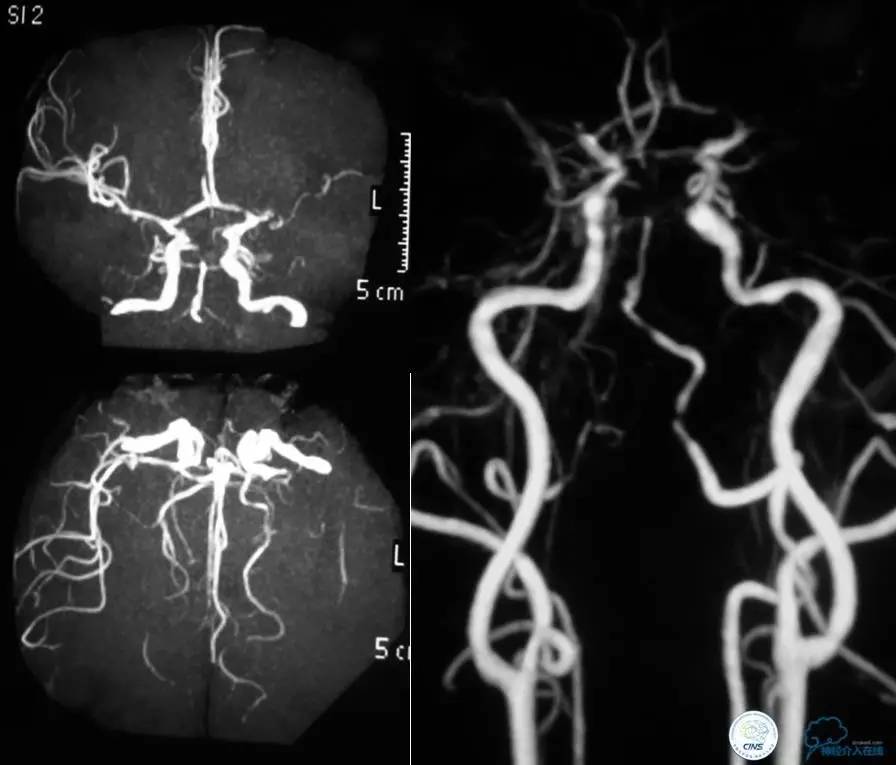

▼第三天MRA